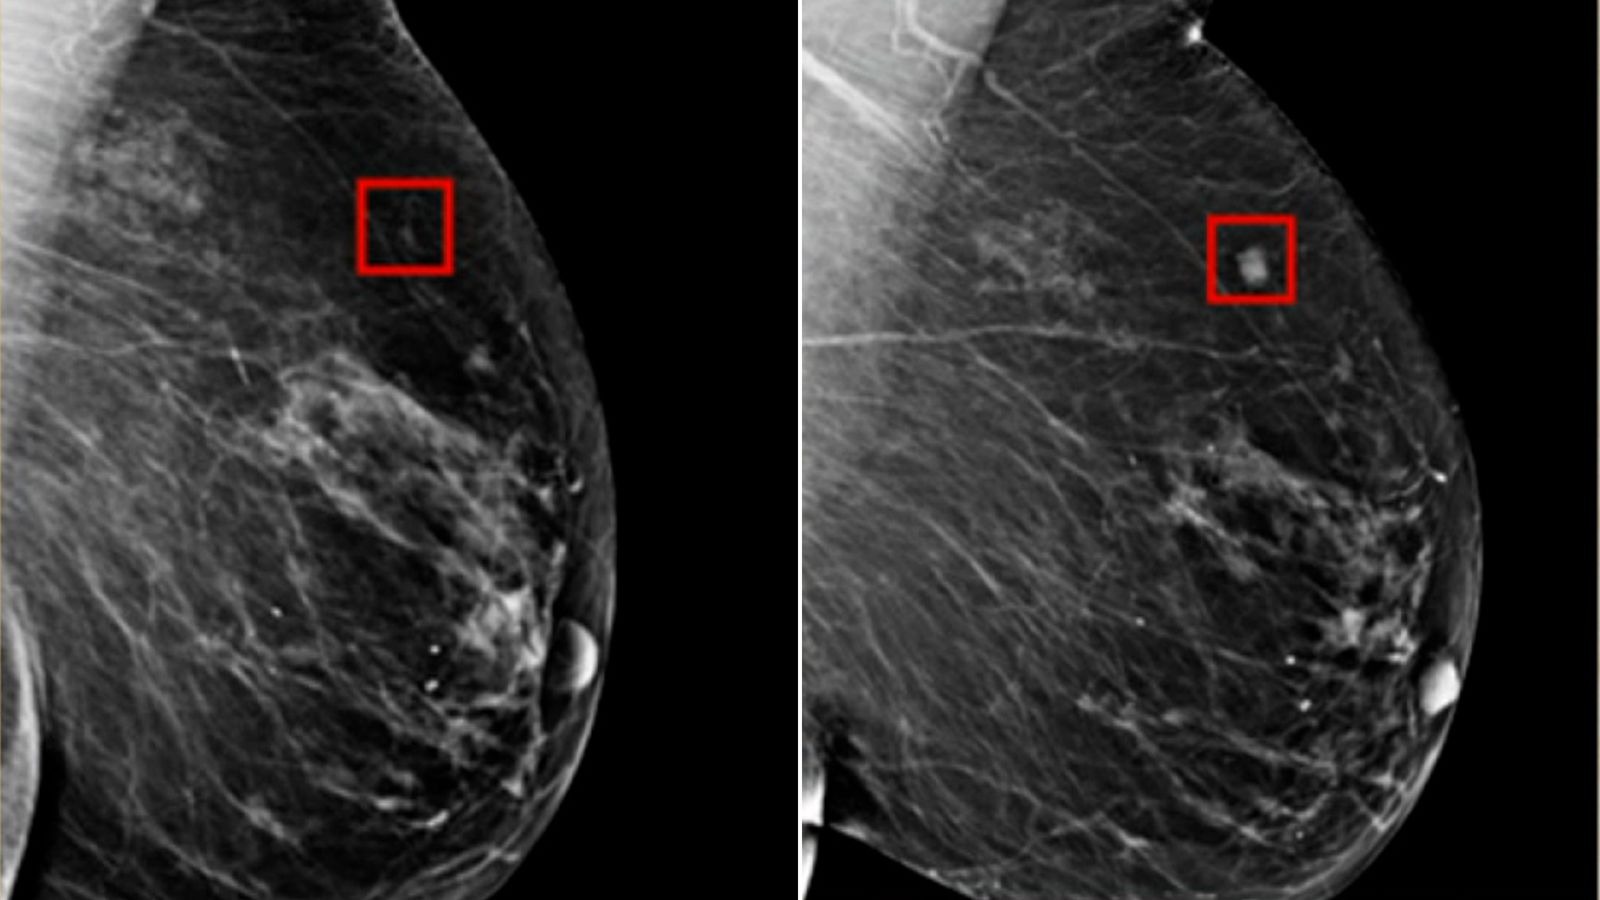

Cervical cancer is one of the most common cancers affecting women worldwide, yet it is also one of the most preventable. According to the World Health Organization (WHO), approximately 600,000 women are diagnosed with cervical cancer each year, and over 340,000 lose their lives to it. The encouraging news is that with proper education, regular … Read more